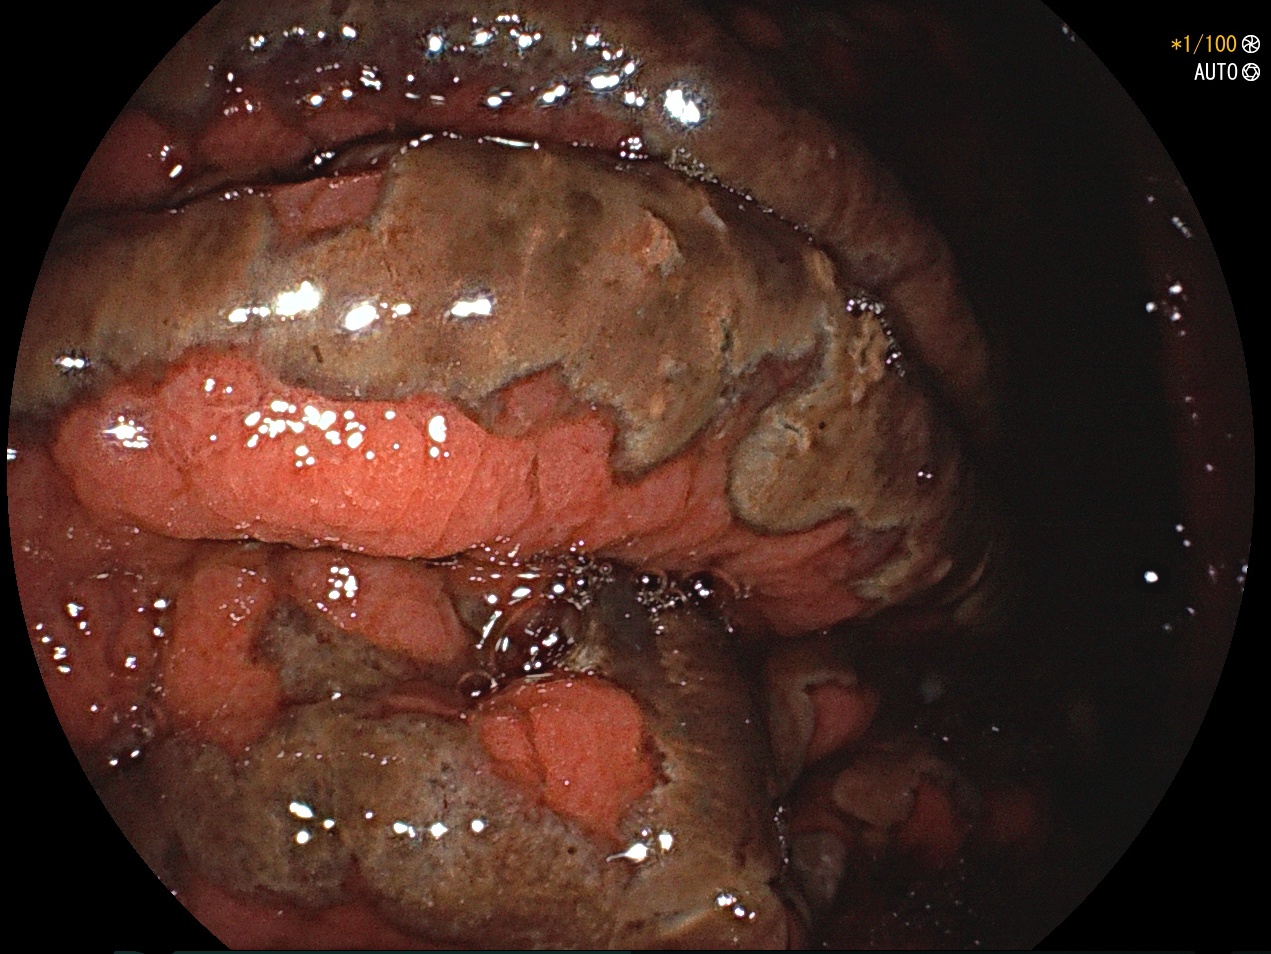

More than recreation – a rare case of cannabinoids effects

Andrea Silva; Margarida Ferreira; Pedro Figueiredo

Centro Hospitalar e Universitário de Coimbra

A 66-year-old male was admitted in emergency room for syncope followed by seizures. Electrocardiogram revealed complete heart block justified by the presence of benzodiazepines and cannabinoids in urine analysis. Meanwhile, he presented hematemesis and hematochezia. Esophagogastroduodenoscopy revealed severe mucosal edema and ulcerated lesions in stomach and duodenum, suggestive of acute ischemia. Abdominal computed tomography showed a patent celiac trunk and thickening of the gastric wall and gastric pneumatosis. Arterial vasospasm has been documented and involved in some of the most serious complications of cannabinoids abuse. The hypothesis more likely for these alterations was vascular spasm triggered by substance consumption.